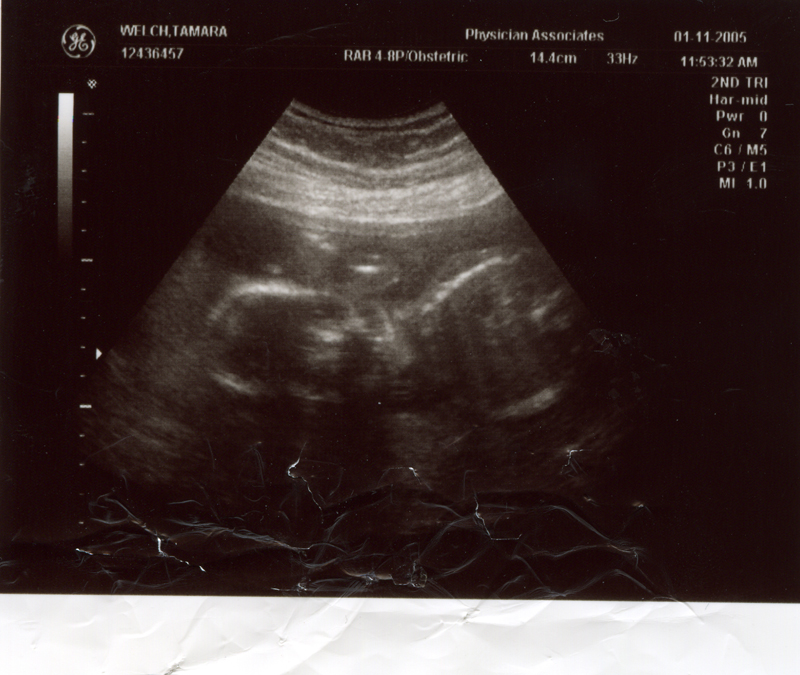

January 11, 2005 - Went to the doctor and had another ultrasound because Tammy hasn't been feeling well. It turns out that the baby is doing fine. The doctor told Tammy to take it easy.

December 21, 2004 - We

had our second ultrasound and found out the sex of the baby. It's

a GIRL! We could see her moving around and see the heart beating.

We also heard the heartbeat during the doctor's visit. The heartbeat

is 150 bpm and the weight is 9 oz. Click on the images below to

see the pictures from the ultrasound. In the image titled "It's

a Girl" you can tell it's a girl because there is nothing

between the legs (the legs are in a "V" shape). We are

thrilled that everything is going well. We are planning to name

her Megan Storey Welch.